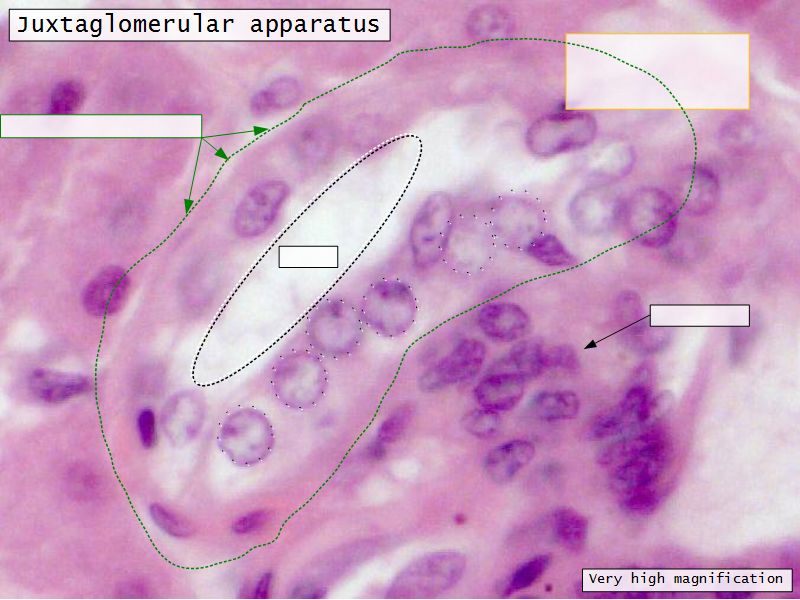

Juxtaglomerular complex

Area where distal convoluted tubule return to glomerulus and pass through the notch between the afferent and efferent arterioles. Modification of the wall of the tubule and afferent arteriole and presence of specialised cells in the connective tissue.Modifications

- Distal convoluted tubule

- Macula densa

- Narrow epithelial cells

- Nuclei densely packed

- CT cells

- Laci cells

- Similar to mesangial cells

- Afferent arteriole

- Modified smooth muscle cells

- Juxtaglomerular cells

- Secretory function

Capillaries

- Supported by

- Mesangial cells

- Mesangial matrix

- Phagocytic

- Maintain basement membrane

- Remove macromolecular deposits

Mesangial cells

- Around capillary loops at vascular pole

- Phagocytic

- Maintain basement membrane

- Remove macromolecular deposits